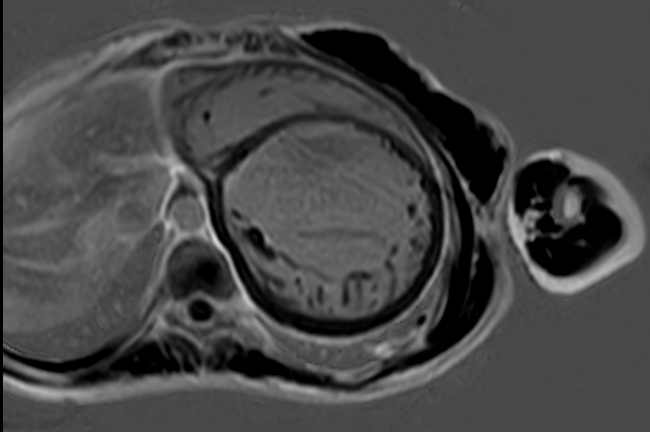

Cine SSFP sequences for morphological and functional evaluation

LGE short-axis images showed a non-ischemic mid-wall pattern in the basal and mid inferoseptal segments.